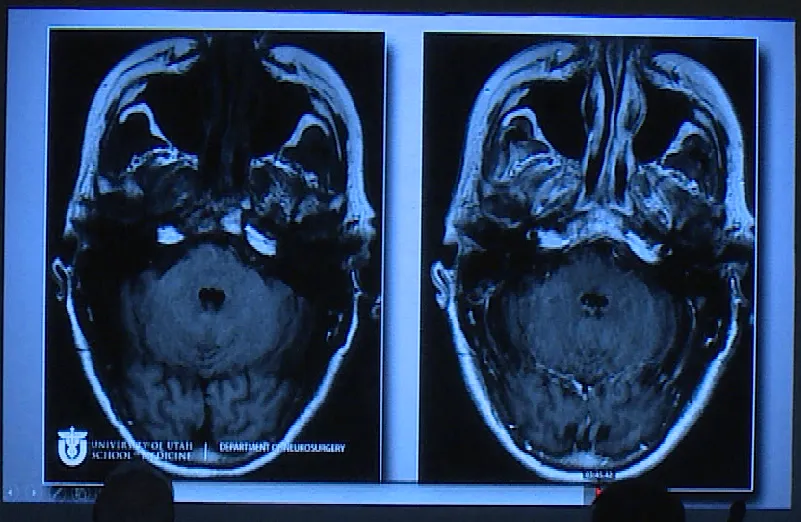

Couldwell教授演講中展示的部分巨大垂體瘤